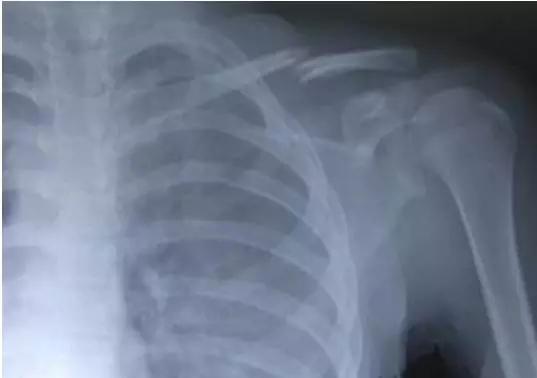

图1:标准的锁骨骨折,此类骨折无需复位。